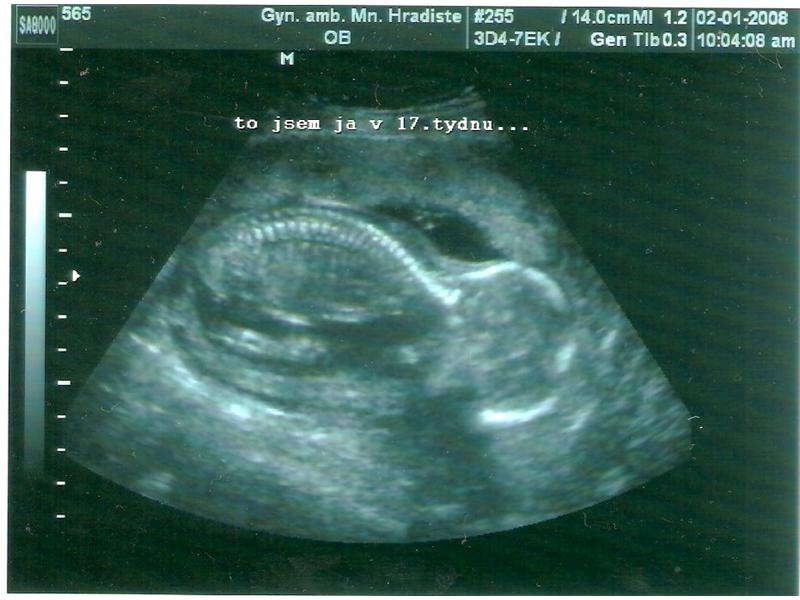

Tak tohle ja naše Natálka,ted ve 17 a pak ve 21 týdnu